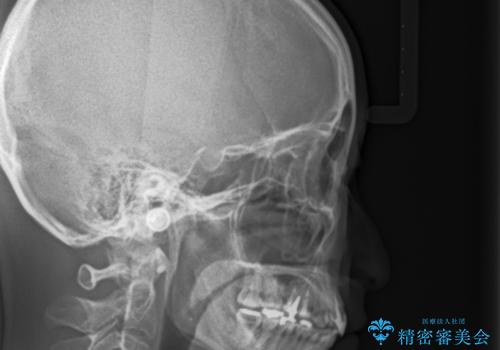

- 前歯の歯並びが気になることを主訴に来院された患者様です。

顎が小さく歯を並べるためのスペースが足りないため、

上下の前歯の歯と歯の間をすく処置(ディスキング)を行いました。

矯正装置:インビザラインフル (初回13stage+リファインメント11stage:計1年)

なお、左下の奥歯(左下7)は状態が悪く保存不可能と判断し矯正前に抜歯しております。